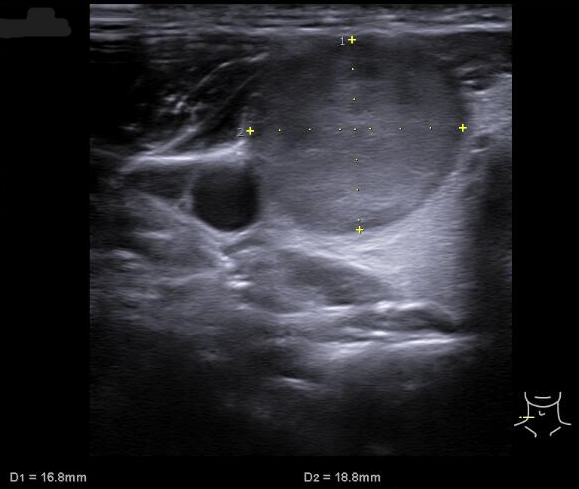

Ecografía tiroidea en AP: En lóbulo tiroideo derecho se aprecia nódulo: hipoecogénico, sólido, con márgenes definidos, sin focos ecogénicos, que presenta vascularización periférica, de morfología ovoide y de dimensiones 32x17x19 mm aproximadamente (CCxAPxT, más alto que ancho). Compatible con TIRADS 4.